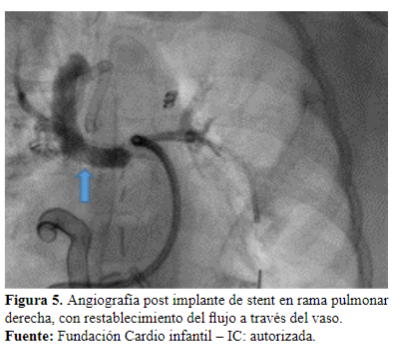

Dos días después es llevada a cateterismo cardíaco para ampliar estudios, donde se evidencia estenosis en la unión de la rama derecha con el conducto (Figura 4). Se realiza angioplastia con stent, queda con buena luz y buen flujo en el pulmón izquierdo (Figura 5y 6).